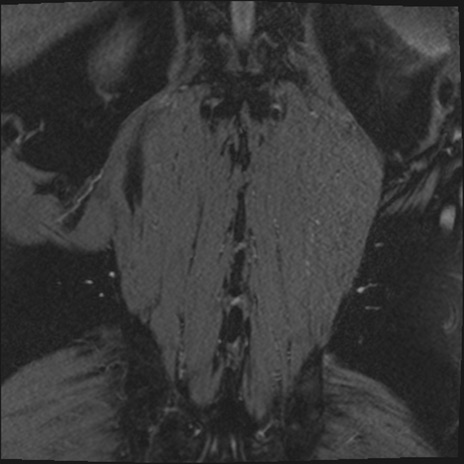

【整形】TIPS症例2 腰椎MRI 3D(冠状断像)

【症例】70歳代男性

【主訴】左下肢痛

【現病歴】2週間前くらいから腰痛、左下肢痛あり。左臀部から大腿、下腿外側のしびれが常時ある。歩行とともに同部位の痛みあり。

【身体所見】Lasegue70-/60+、Bragard-/±、PTR ±/±、ATR -/-、IP 5/5、TA 5/4、TS 5/5、EHL 右第1足趾なし/3、FHL 5/5、hypersthesia(-)、足背動脈触知良好

異常所見と診断は?